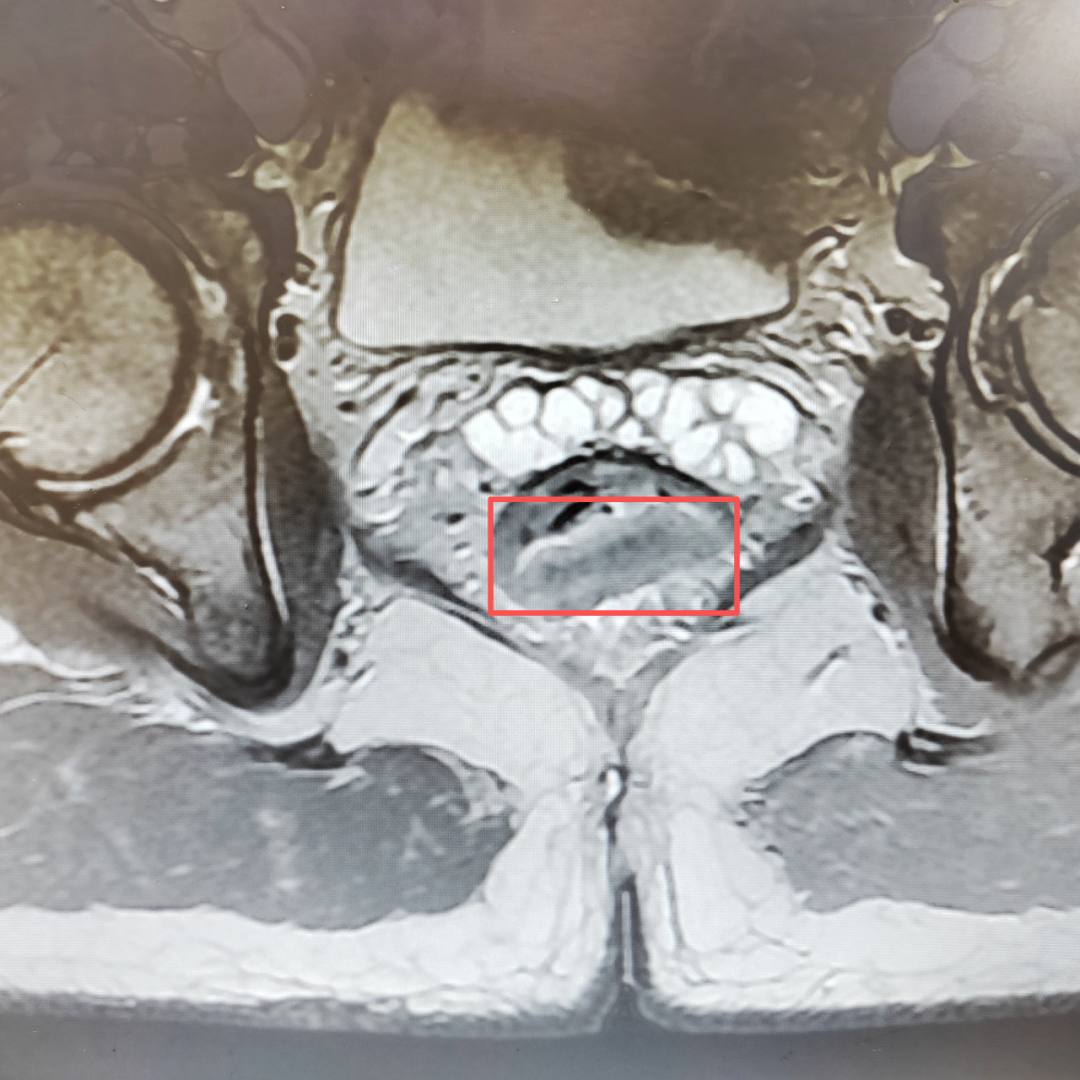

随即到当地医院检查,诊断为“超低位直肠癌”,肿瘤的下缘距离齿状线(直肠粘膜与肛管皮肤之间的交界线)仅2厘米。

接诊后,张超教授团队立即结合全面的检查报告,综合分析王大叔病情。由于发现较早,肿瘤不大且未浸润肛门外扩约肌,患者身体基本情况较好,肛门功能良好。

张超教授团队认为可尽快为其开展腹腔镜辅助经括约肌间直肠癌根治术(ISR)。这一消息对于王大叔一家,像黑暗中的一束光。

盆腔狭小的空间里结构复杂,有大量的神经、血管、肌肉和筋膜。手术对术者技术要求非常高。